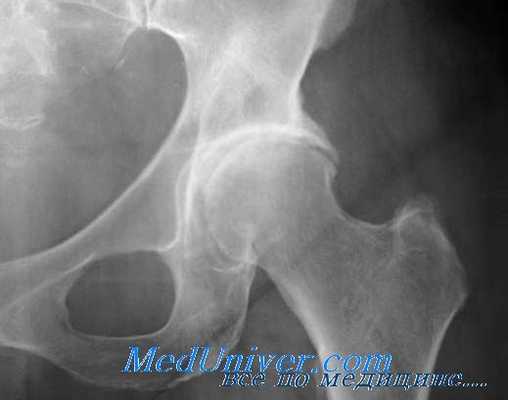

Рентгенологическое исследование

Стадия коксартроза устанавливается проведением рентгенографического исследования. На полученных изображениях отчетливо просматриваются деструктивные изменения в тазобедренном суставе. Это сужение суставной щели, деформация костных поверхностей, формирование остеофитов.